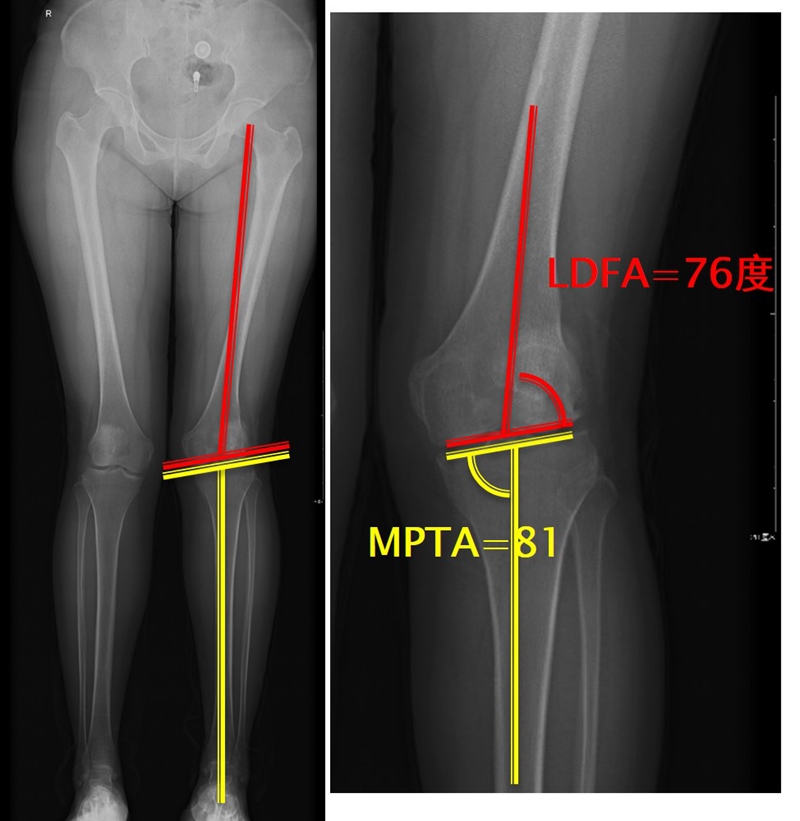

画下肢机械轴,股骨头中心链接踝关节中心判断患者为内翻畸形还是外翻畸形。此患者为外翻畸形。

步骤二:判断畸形部位

量股骨远端外侧角和胫骨近端内侧角,判断畸形在股骨、胫骨还是关节内。此患者股骨侧有畸形,LDFA=76°,MPTA=81°,无关节内畸形。